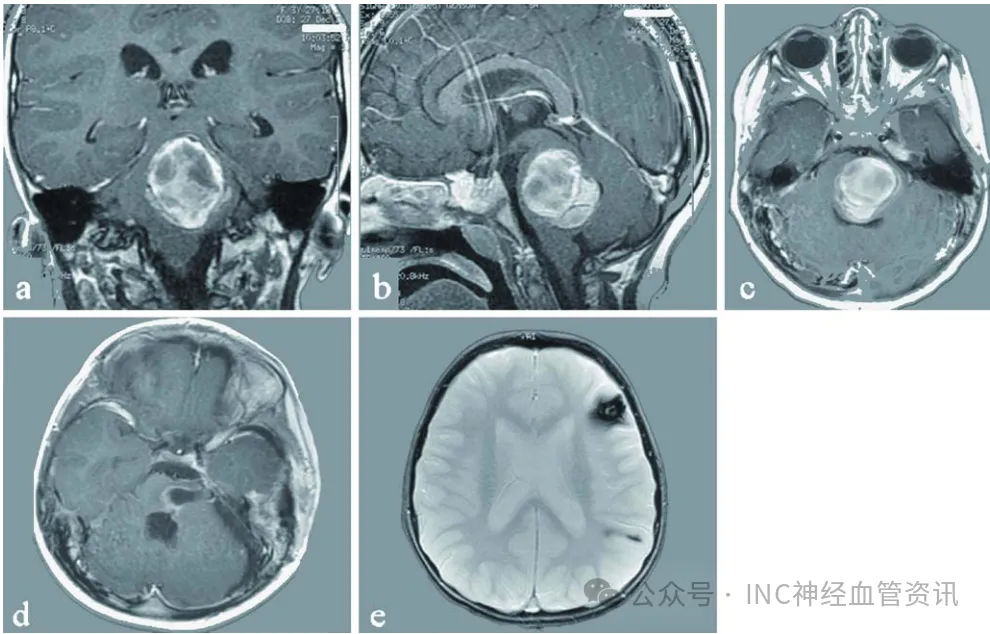

淼淼父母观察到孩子出现一系列异常表现:临床表现为嘴角歪斜、流口水及斜视等症状,这些均为既往未曾出现的体征。经医院系统检查,确诊为颅内巨大海绵状血管瘤,该病灶已引发脑干出血。...

更新时间:2025-12-01 10:52:50